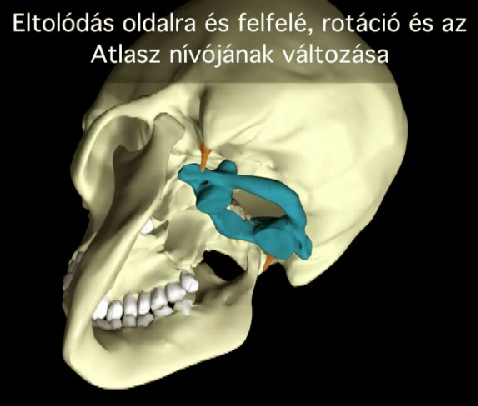

Súlyos testi és lelki panaszainak megoldását keresve René Claudius SCHÜMPERLI az 1993-1996-ig tartó intenzív kutatásai során rádöbbent arra, hogy a koponya-atlasz ízületben az Atlasz (első nyakcsigolya) szinte minden embernél ficamszerűen elfordult állapotban van. Megállapította azt is, hogy az atlasz elfordulását változó mértékű elbillenés is kíséri. Tehát a koponya alátámasztottsága nem vízszintes, és változó mértékű és súlyosságú egyensúlytalanság lép fel. A […]]]>

Súlyos testi és lelki panaszainak megoldását keresve René Claudius SCHÜMPERLI az 1993-1996-ig tartó intenzív kutatásai során rádöbbent arra, hogy a koponya-atlasz ízületben az Atlasz (első nyakcsigolya) szinte minden embernél ficamszerűen elfordult állapotban van. Megállapította azt is, hogy az atlasz elfordulását változó mértékű elbillenés is kíséri. Tehát a koponya alátámasztottsága nem vízszintes, és változó mértékű és súlyosságú egyensúlytalanság lép fel. A […]]]>

Elbillent Atlasz A Magyar AtlasPROfilax Társaság hivatalos honlapja és a specialisták megtekinthetők a http://atlaszprofilax.com honlapon. A világ 30 országában mintegy 350 specialista jogosult alkalmazni ezt a különleges eljárást, amit a svájci René Claudius SCHÜMPERLI dolgozott ki 1993-1996-ig. Az ATLASPROFILAX® egy speciális lágyrész wellness-masszázs kezelés, ami az első nyakcsigolya normális pozícióba való visszatérését teszi lehetővé. A feltaláló a világon elsőként észlelte […]]]>

Elbillent Atlasz A Magyar AtlasPROfilax Társaság hivatalos honlapja és a specialisták megtekinthetők a http://atlaszprofilax.com honlapon. A világ 30 országában mintegy 350 specialista jogosult alkalmazni ezt a különleges eljárást, amit a svájci René Claudius SCHÜMPERLI dolgozott ki 1993-1996-ig. Az ATLASPROFILAX® egy speciális lágyrész wellness-masszázs kezelés, ami az első nyakcsigolya normális pozícióba való visszatérését teszi lehetővé. A feltaláló a világon elsőként észlelte […]]]>